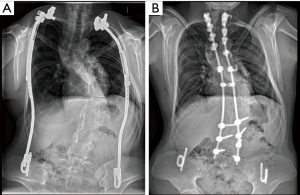

Despite the progress made, growth-sparing surgery for EOS patients with distraction-based implants predominantly remains a delaying-fusion strategy. While there are numerous reports on results and outcome during ongoing VEPTR treatment, not much information on definitive procedures at the end of growth in EOS patients is available. The paucity of reliable data and the heterogeneity of EOS patients restricts the decision-making process for so-called “graduates” of growth-sparing surgery. Many times, the decision about when to stop expansions is less surgeon-driven, but rather determined by curve progression, failure to further distract, or complications (20,21). In 2013, Flynn et al. were the first to report a multicentre series of 99 graduates of tGR treatment (22). Two other reports from the Growing Spine Study Group (GSSG) focused on EOS patients after tGR and Shilla growth guidance treatment, with the former focusing on the possibility of avoiding final surgical fusion (23,24). Johnston et al. reported on the functional and radiographic outcomes of 12 patients following growth-sparing management, including one VEPTR patient, while Sawyer et al. looked at complications and radiographic outcomes of 37 patients after distraction-based treatment, in which 32 had rib-based fixation without specification of the type of implant (25,26). Regardless of the type of implant, the results were mostly modest with frequently low correction potential and high complication and reoperation rates with final fusion. Recently, we published a study on the radiographic outcome and complication rate of 34 of our own VEPTR graduates (27). The mean age at the end of VEPTR treatment was 13.8 years, with 50% of the graduates following a non-fusion strategy. In 5 patients with congenital EOS and unilateral VEPTR constructs the implants were simply removed (Figure 5), and in 12 patients the VEPTR was left in situ. So far, no further complications have been observed over an average follow-up period of 41 months in the non-fusion group.

Seventeen patients underwent final fusion surgery (Figure 6).

Younger age at first VEPTR implantation and higher major curve’s and main kyphosis’ Cobb angles at the end of VEPTR treatment were parameters that reached statistical significance between patients undergoing final fusion surgery and patients following a non-fusion strategy. There was a 41% complication rate in the final fusion group over a mean follow-up period of 25 months, leading to 6 unplanned returns to the operating room. For final fusion surgery, a 14% average correction rate of the main coronal deformity was achieved. This is even lower compared to the limited correction rate reported by Flynn et al. in their series of tGR graduates (22) and might be explained by the presence of ossifications of the thorax in rib-based implants in addition to the spontaneous autofusions of the spine. The considerable complication rate and occurrence of rigid deformities of the spine and the thorax suggest that final fusion procedures should be avoided. Satisfactory axial alignment and balance are minimum prerequisites for this, but the current lack of mid- and long-term follow-up of graduates without final fusion do not yet allow any firm conclusion to be drawn (24).